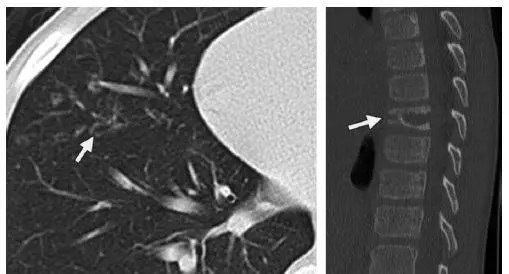

早期疾病薄层断层扫描(CT)可显示1–10mm的小叶中心结节或者空洞(图1)。随着病情的发展,囊性病变逐渐取代结节,表现为厚或薄壁囊腔,形态多不规则(图2)。结节和囊性病变通常累及双肺上中野,肺尖和肺底以及肋膈角常不受累。约25%的患者由于胸膜下囊腔破裂导致自发性气胸,累及双侧并且可以反复发作,这是本病的首发症状(图3)。终末期疾病的特点是肺过度充气以及广泛的囊腔,形成终末期肺气肿(图4)。薄层CT具有特征性人口统计学分布特点及临床表现,是PLCH临床诊断的重要依据,从而避免肺活检。在儿童中,薄层CT表现与成人相似,但更病变更广泛(图5),并且与未发现与吸烟有关的病灶。

图5 9岁男性LCH患者。轴位CT(a)显示右肺中叶(箭头)和舌叶(未显示)的囊腔和小叶中央结节。(b)胸椎矢状位CT显示中段胸椎椎体塌陷,由LCH引起